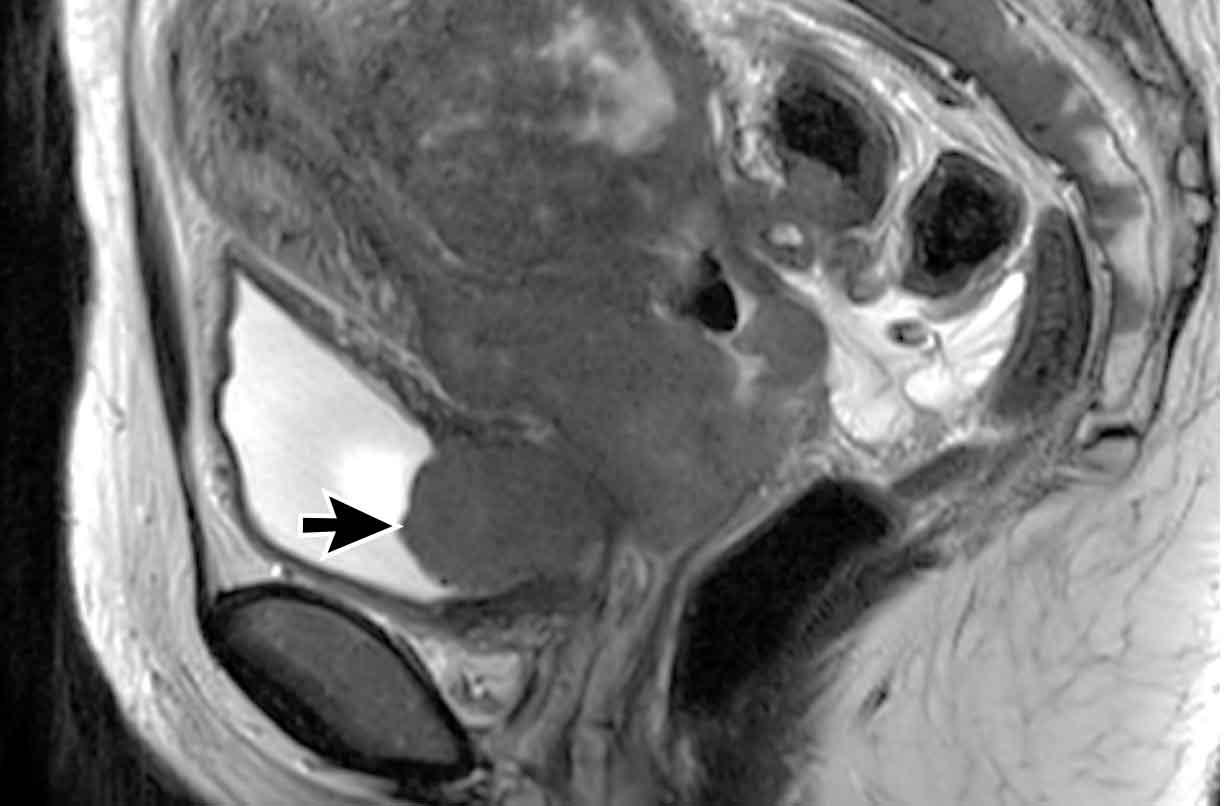

Trong một số ít trường hợp, phác đồ điều trị chuẩn gồm hóa xạ trị đồng thời kết hợp xạ trị áp sát không đủ hiệu quả và nghi ngờ còn tổn thương tồn lưu, như minh họa trong ví dụ dưới đây.

Hình ảnh

MRI trước điều trị (bên trái) cho thấy khối u cổ tử cung dạng sùi với tín hiệu trung gian (mũi tên đen).

MRI sau điều trị (bên phải) cho thấy một khối tín hiệu trung gian trên T2 tồn lưu nhỏ nhưng quan sát rõ ràng, cho thấy khối u chưa được thay thế hoàn toàn bởi mô xơ (mũi tên trắng).

Bệnh nhân được chỉ định phẫu thuật, đây là phương pháp điều trị chuẩn cho các bệnh nhân có đáp ứng không hoàn toàn sau hóa xạ trị đồng thời kết hợp xạ trị áp sát.

Chuỗi xung DWI có thể hỗ trợ phát hiện u tồn lưu sau hóa xạ trị đồng thời.

Lưu ý rằng thời điểm được khuyến cáo để đánh giá đáp ứng sau hóa xạ trị đồng thời là từ 4 đến 6 tuần sau khi kết thúc điều trị.